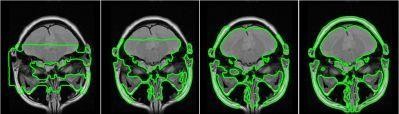

Contour propagation by initial conditions (40, 100, 150 and 200 iterations)

For efficient and robust segmentation of various anatomic structures we implemented the Chan-Vese- algorithm (a deformable model with Level Sets).

The Chan-Vese algorithm is a deformable model approach with contour evolution based on the Mumford-Shah functional, and the level sets of Osher and Sethian.

First applications with specific anatomical structures (brain, vessels, spine) led to robust and accurate segmentation results. And a strength of the algorithm is its ability to handle the topology changes (level sets).